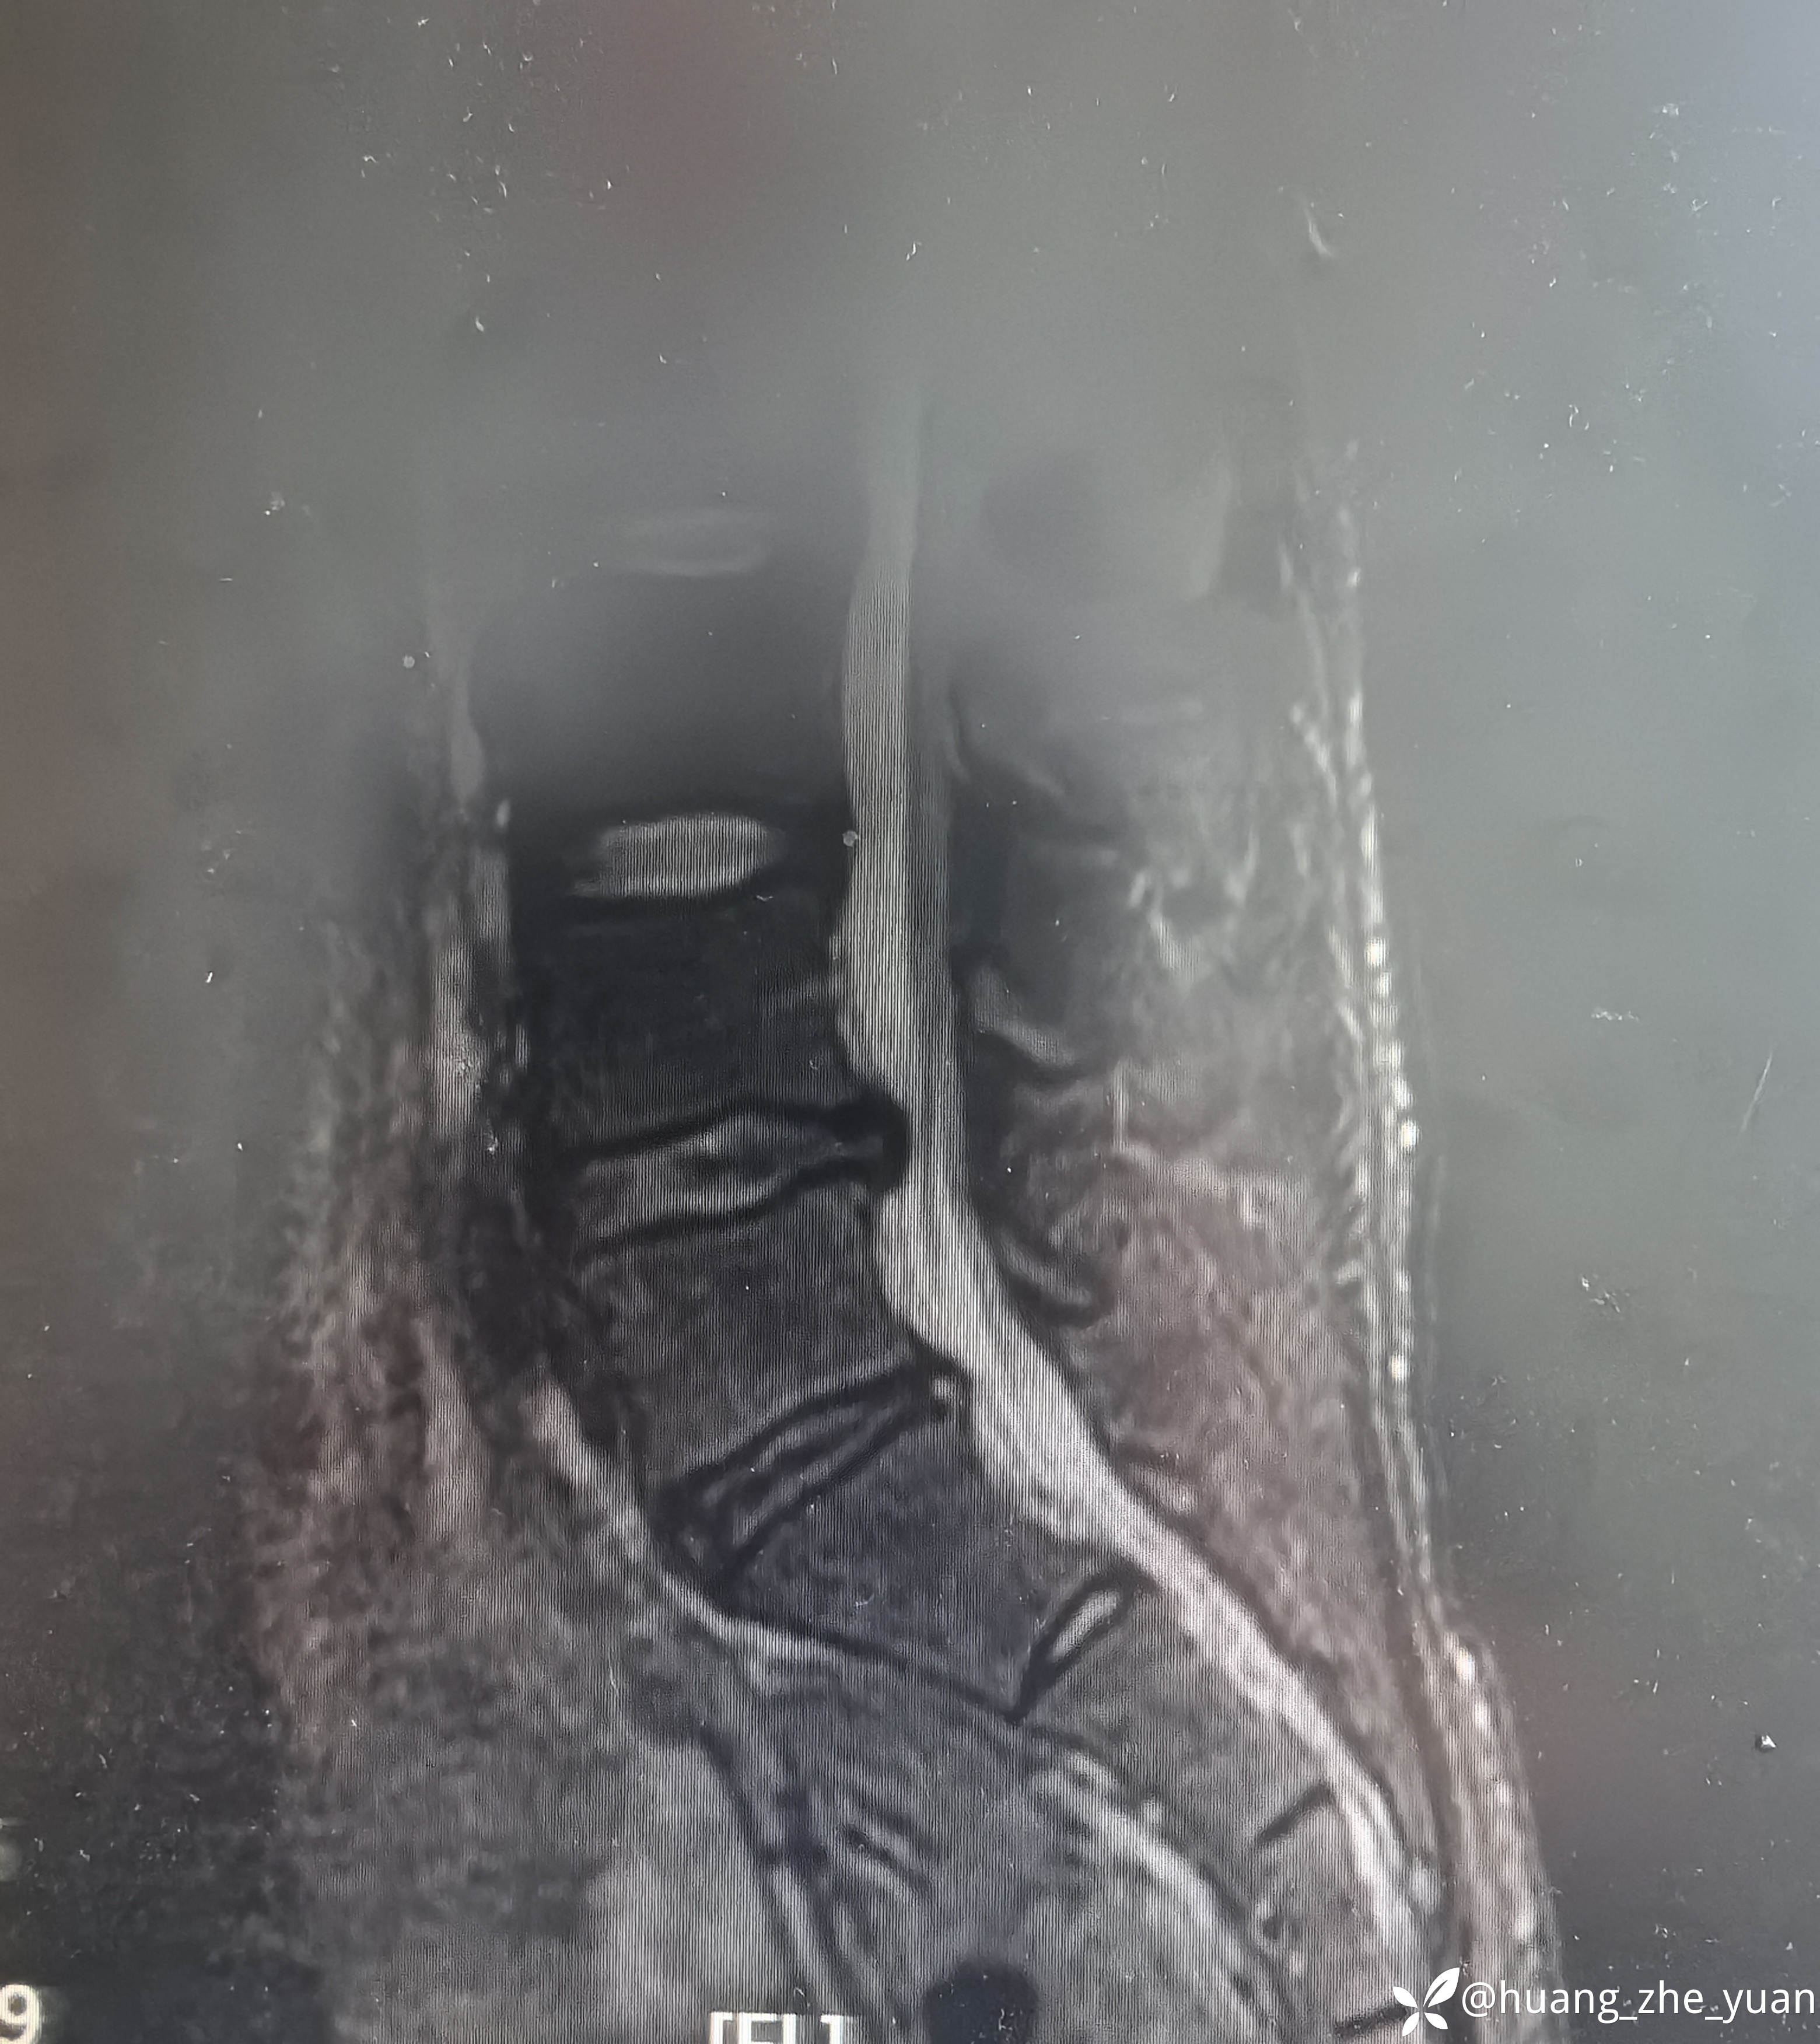

术后腰痛完全缓解,叩击无痛。术前无法忍受叩击。